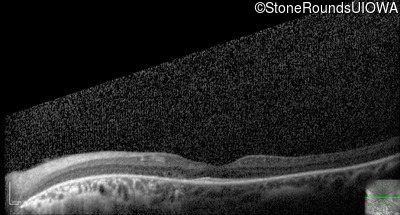

Optical Coherence Tomography - Right - 20/63 +2

Exemplar / OCT Stack

OCT Stack